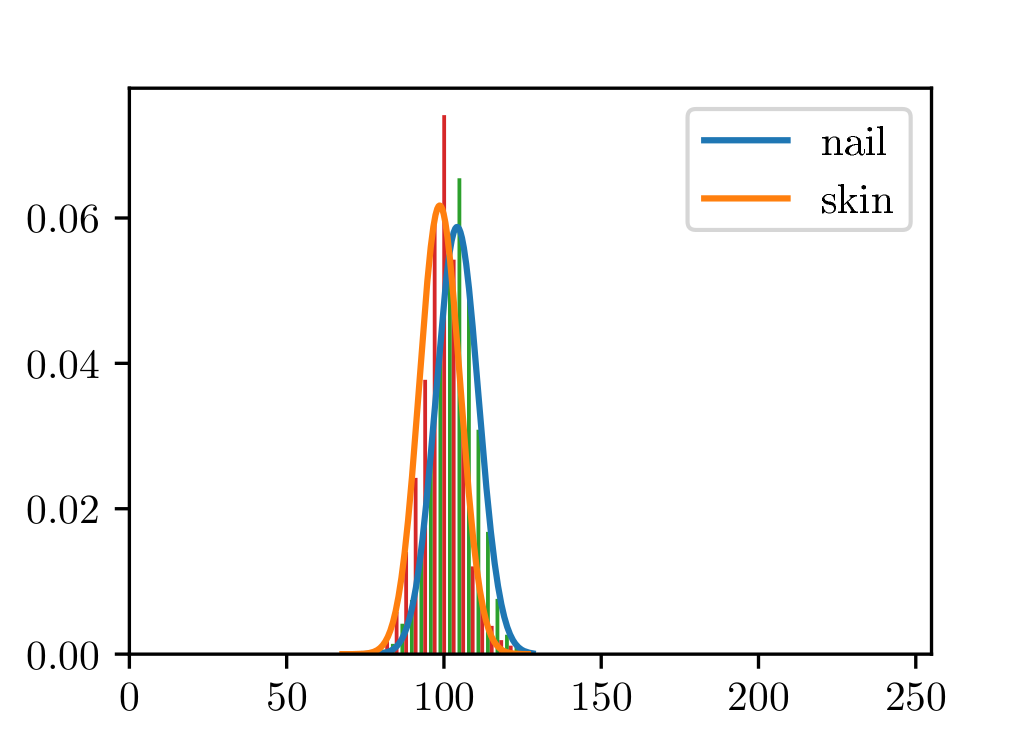

The photometric properties of nail pixels do not contain enough information to segment them from toe ones. In Fig. 1 we group pixels belonging to the nail region and the toe region, respectively. We observe that their distribution across different channels of the CIELAB color space is very similar. In fact, none of the channels, nor a combination of them, has proved to be enough to tell apart these pixels, especially when considering pictures taken under different illumination conditions. Thus, although nail and toe can be easily discriminated by a human observer, doing so based only on pixel-based local information poses as an arduous challenge.

The colorimetry represents the larger group of features used by the training models. The two most informative ones in this group are the mean and the standard deviation of the a channel from the CIELAB color space.

Nail and skin can not be segmented using only color or local information. The pixel-wise colors of human nails are indistinguishable from those belonging to toes (see Sect. 2). This is specially important when dealing with different skin shades or illumination conditions. We can not, however, disregard photometric information (see Fig. 9).